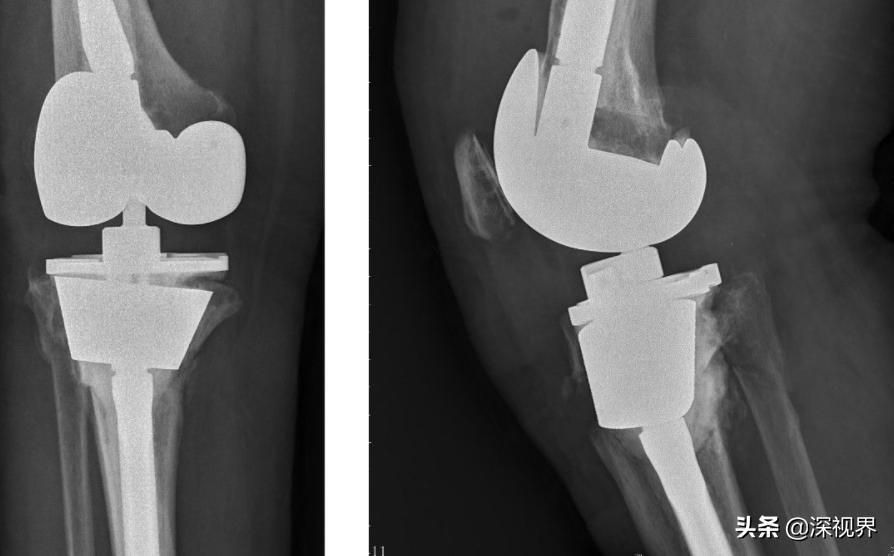

虽然在医学领域中,有很多新技术应运而生,但想要彻底替代传统人工手术,是一件无法实现的事情。就像我们看到的人工关节置换术,现在并没有可以替代的机器人手术技术。机器人做手术,本身它就是有局限性的,它只是在某个方面具有非常大的优势,是我们人工无法替代的,但对整台手术的把控,还是需要人工完成。

图为人工关节置换术